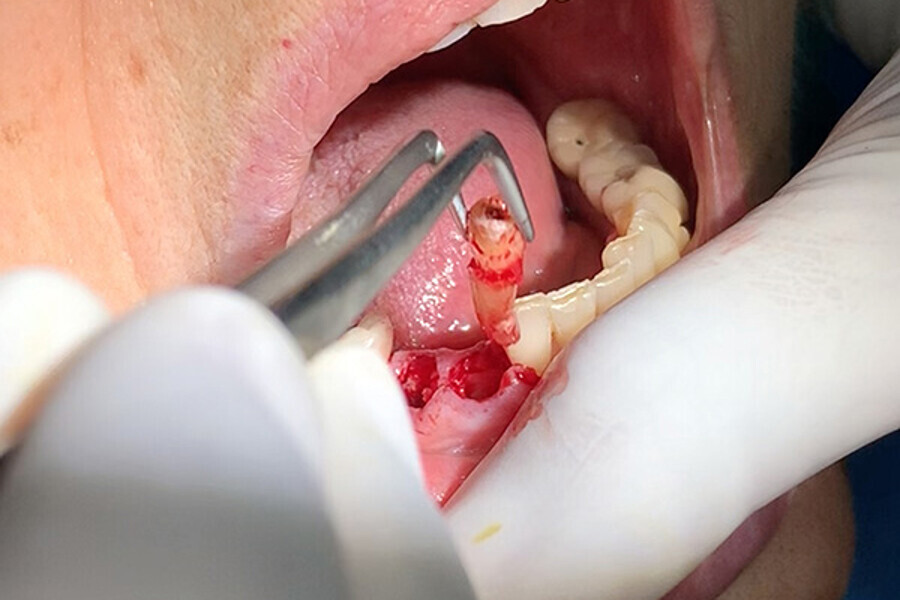

Figs. 7. Remoción delicada de los restos radiculares y comproba

Figs. 8. Remoción delicada de los restos radiculares y comproba